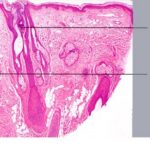

Traction Alopecia Traction alopecia is another type of mechanical alopecia, usually resulting from a variety of hair-styling practices, particularly in African-Americans, that includes tight braids, corn rows, straightening, and the use of sponge rollers . Hair follicle injury is similar to that produced in trichotillomania, but in traction alopecia there are differences that relate to the use of less force over a greater period of time (194). Traction alopecia is often classified clinically and histologically as "early" and "late" disease . In early disease, tension on hair follicles exists over the course of months to a few years, sometimes presenting as a traction folliculitis with perifollicular erythema and pustules . In late disease, hair is subject to traction over many years. In early disease, discontinuation of the abnormal forces on the hair leads to regrowth of hair, but in late disease, follicles are lost, producing a permanent alopecia. Early and late disease are commonly found together in the same patient; as permanently scarred areas develop (late disease), terminal hairs at the periphery are used in styling, becoming the new target of traction (early disease) (. Occupationally related traction alopecia has been reported due to wearing of a nurse's cap, occurring at the site of pin placement used to secure the cap . Histopathology. In early traction alopecia, the histologic findings are similar to those of trichotillomania, albeit more subtle (194). For instance, the density of follicles is normal, with a normal number of vellus hairs. Premature conversion of anagen hairs to catagen occurs, resulting in an increased number of catagen and telogen follicles. Pigment casts and trichomalacia are sometimes found, although less often than in trichotillomania. Inflammation is absent. |

outnumbering terminal follicles. In late |

disease, the pathology shows an "end-stage" scarring alopecia, a histologic picture shared by many forms of permanent alopecia at an advanced stage. Pigment casts and trichomalacia are not seen in late traction alopecia. |